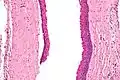

التشخيص النهائي عن طريق التحليل النسيجي ، أي الاستئصال وفحصها تحت المجهر . تشبه الأغشية الحرشفية الكيراتينية بغموض .[2]

ومع ذلك فإنها تفتقر إلى الحواف , و غالبا ما يكون هناك تحت المجهر , غالباً فصل انفصال عن الغشاء القاعدي المحيط بهم .

Intermed. mag.